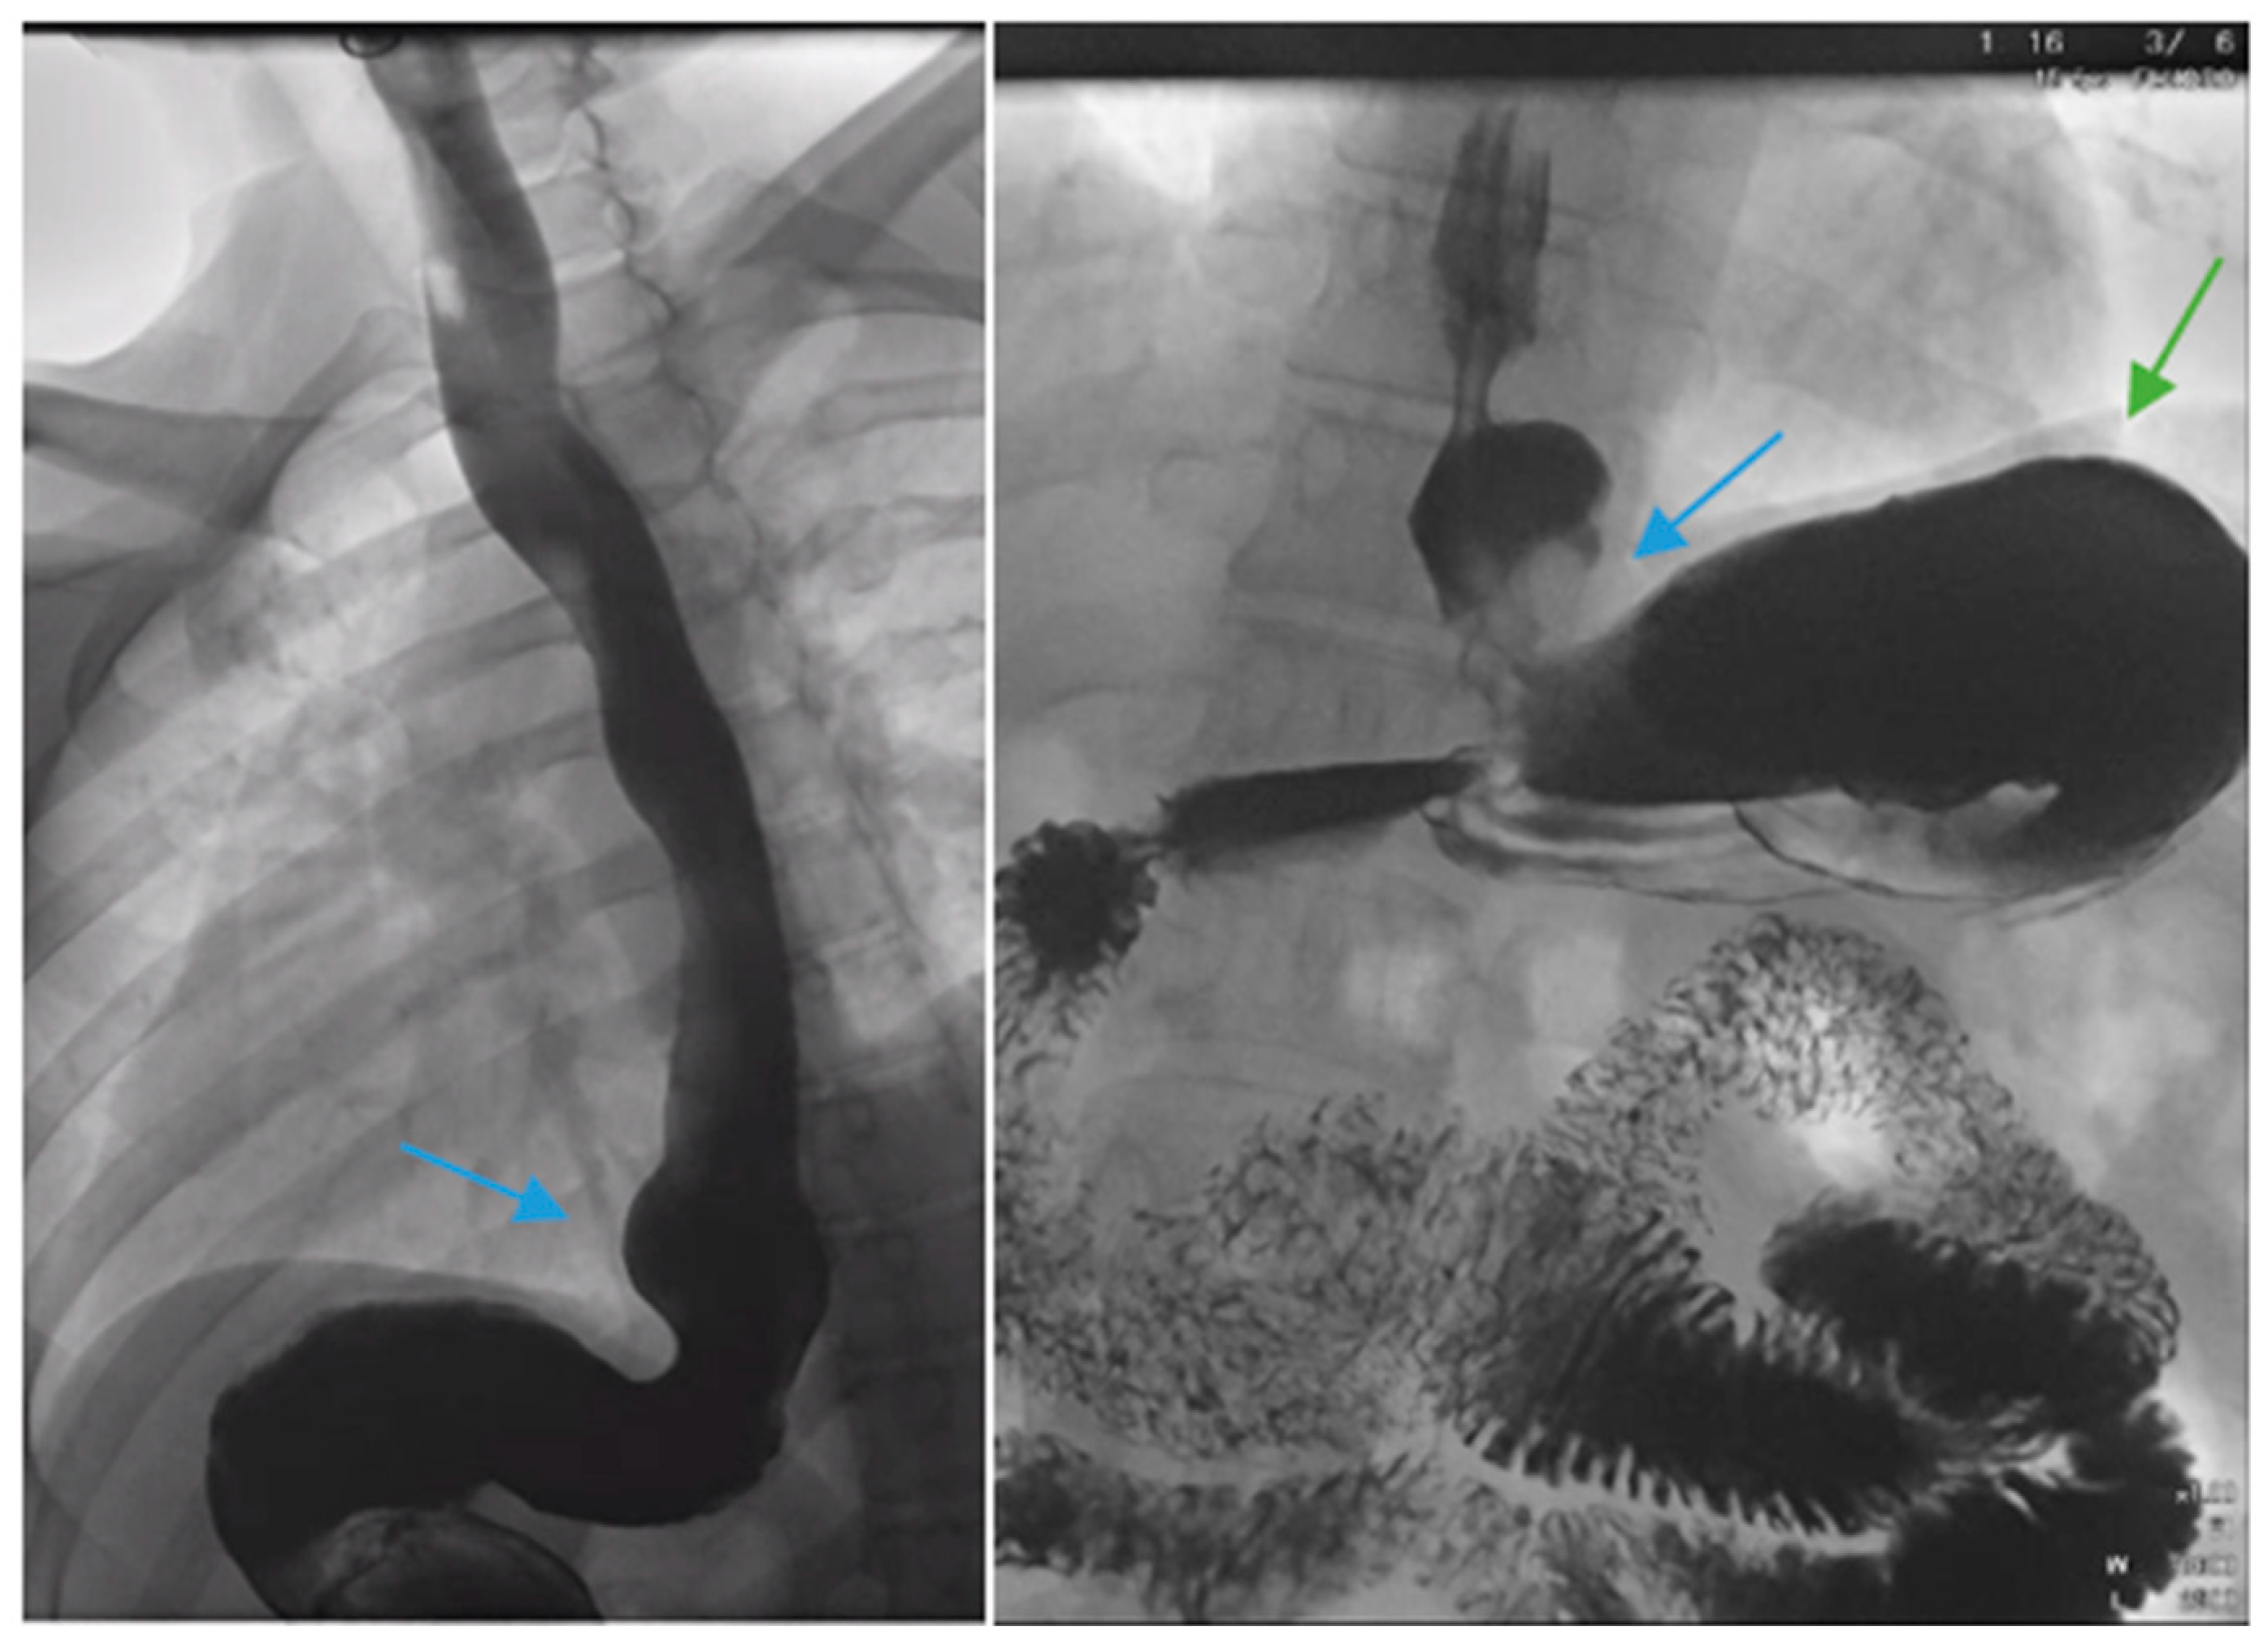

Figure 1.

Upper gastrointestinal series in a patient post-sleeve gastrectomy with early satiety and reflux reveals the following: a small, hiatal hernia and gastroesophageal reflux (blue arrow, left) in addition to abnormal angulation (blue arrow, right) and dilation of the gastric sleeve (green arrow, right). The patient underwent conversion to Roux-en-Y gastric bypass with marked clinical improvement.

Complications of SG, including stenosis, angulation or kinking, are associated with increased intragastric pressure and GERD (Figure 1) [38]. Data regarding the optimal bougie size for weight loss and reduced reflux are mixed, but generally support a range of 36–42 French [39,40,41,42,43]. Overfilling of the gastric sleeve due to a large meal portion may result in reflux symptoms, and thus, patients should be counseled to gradually advance their diet from liquids to small portions of healthy, protein-rich foods. The gastric sleeve dimensions should be sufficient, as too narrow of a gastric sleeve may result in increased intragastric pressure and subsequent reflux. An abnormally narrow sleeve may also lead to regurgitation due to overfilling, even in patients with a competent lower esophageal sphincter and no hiatal hernia. Felinska et al. described the ideal shape of a gastric sleeve to be a trapezoid with a wide antrum and a narrow cardia to prevent sleeve stenosis or increased pressure within the stomach [34]. Furthermore, the preservation of the antrum has been suggested to increase gastric emptying and reduce subsequent GERD [44]. Esophagogastric dysmotility may be a contributing factor to post-SG GERD and a dynamic contrast study can be a useful test in establishing the diagnosis.